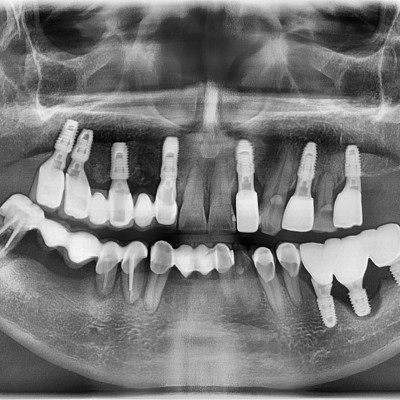

임플란트 재수술

임플란트 재수술 #12.13.22 타원 임플란트 제거 후 임플란트 수술+치조골 이식술 시행하였습니다.

임플란트 재수술 #44.45.46.47 타원 임플란트 보철물 제거 후 임플란트 재수술+치조골 이식술 시행하였습니다.

임플란트 재수술 #14.15.16.17 타원 임플란트 제거 후 임플란트 식립+ 치조골 이식술 시행하였습니다.